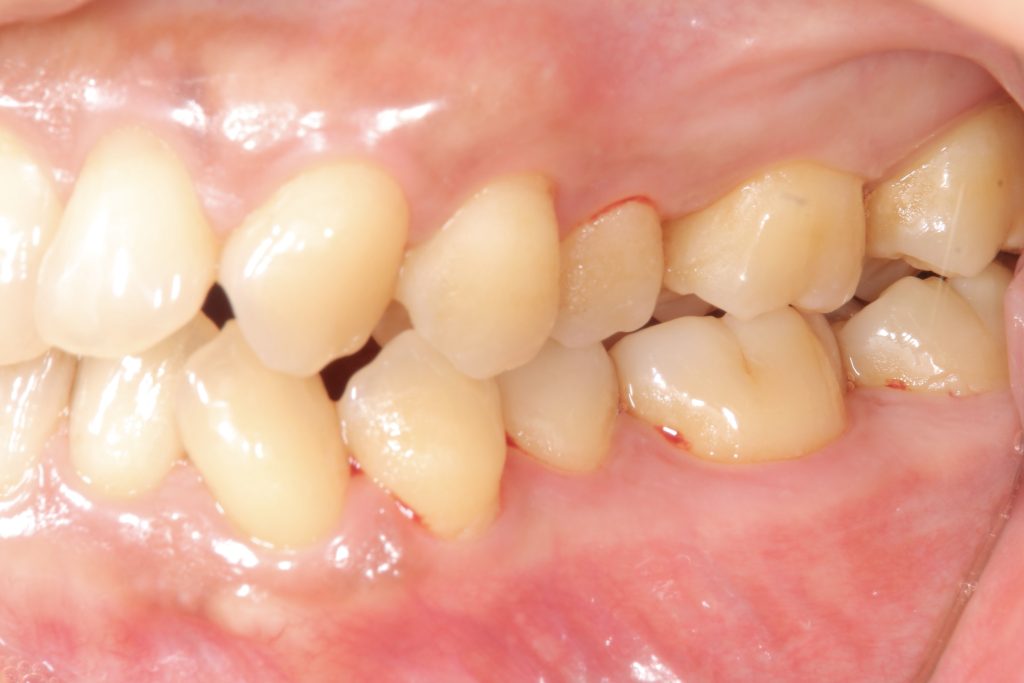

受け口の状態により、上の歯が内側に入り込み、反対の噛み合わせになっている部分が見られました。見た目の問題だけでなく、噛み合わせのバランスにも影響を与えていました。

- 前歯部交叉咬合を伴う不正咬合

- ゴムメタルワイヤー矯正

- 2024年9月6日(10ヶ月)